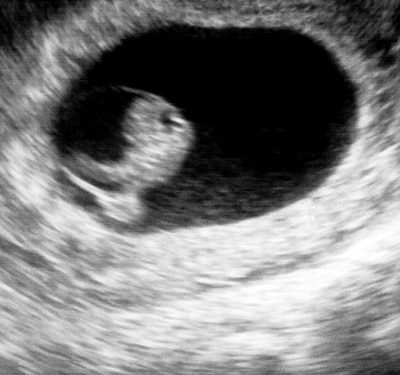

In questo breve volumetto tascabile l’autore Gino Cuda, coadiuvato dalle più recenti indagini scientifiche, proverà a far emergere il vero statuto ontologico dell’embrione umano. Tenterà, quindi, di chiarire se l’embrione possa essere considerato o meno un vero soggetto umano, depositario dunque di quei diritti inalienabili comunemente attribuiti agli individui.

Le argomentazioni proposte dell’autore ripropongono in modo oggettivo i risultati scientifici più recenti. All’interno del libro è possibile trovare anche la posizione ufficiale della Chiesa cattolica sull’aborto, già espressa in molti documenti ecclesiali e sintetizzata all’interno del testo.